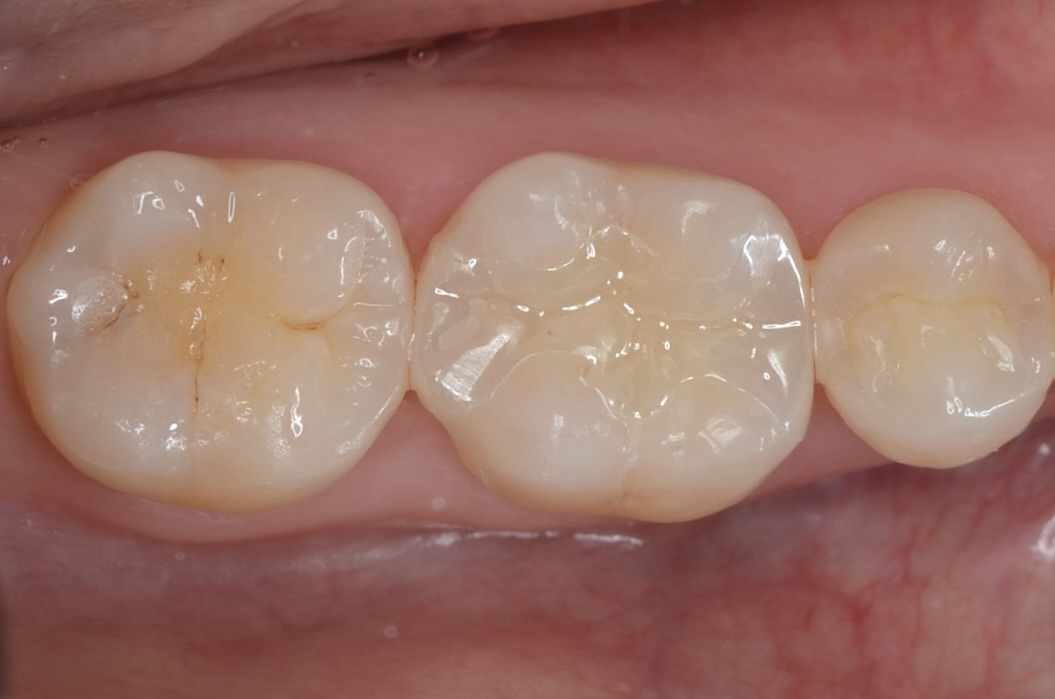

Before

After

研磨終了

噛み合わせの調整をした後に、」段差の部分をしつこく研磨します。 -

-